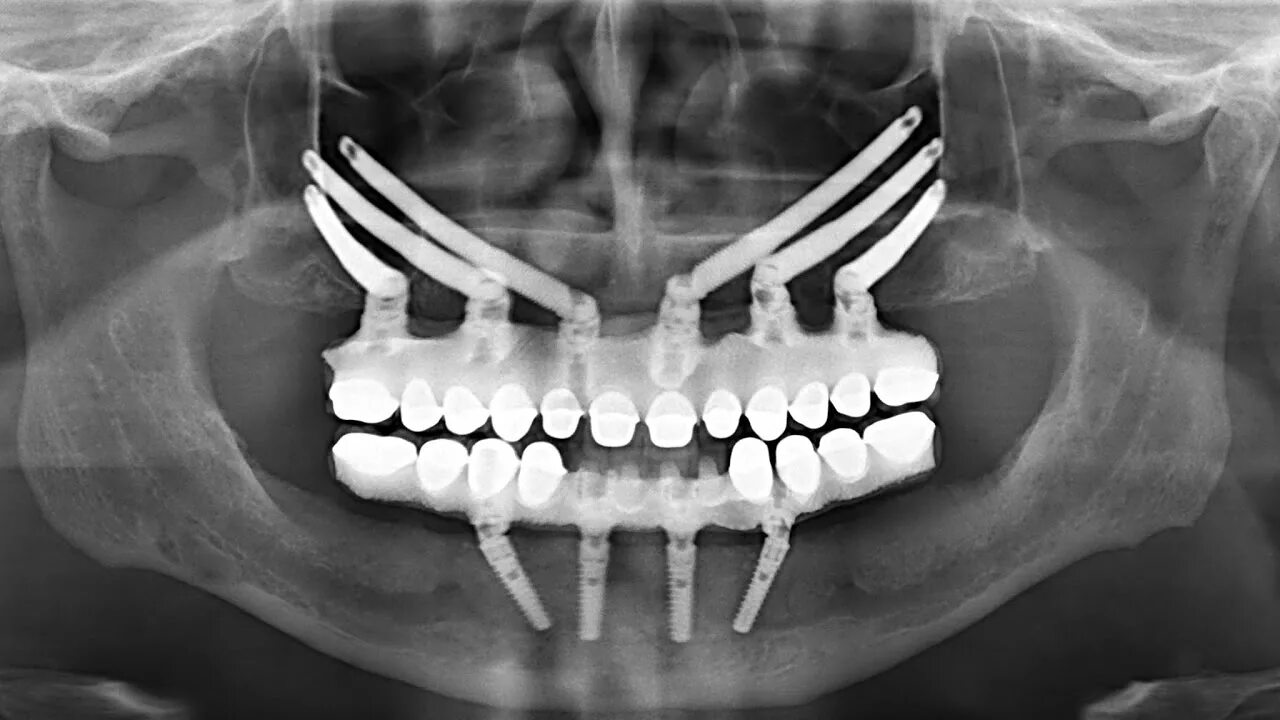

All in установка